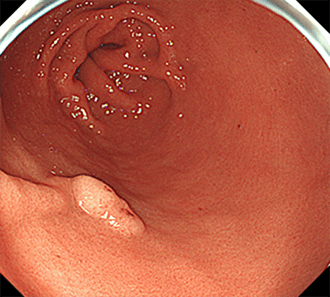

胃過形成性ポリープピロリ菌に感染している萎縮性胃炎を背景に発生することが多く、感染の指標にも成り得るといえます。また広義の腺窩上皮型過形成ポリープには、血管・間質の増生を伴わない単純な腺窩上皮の増殖によるポリープもあります。このようなものはピロリ菌未感染胃や除菌後胃に見られることも多く、春間-川口病変(多発性白色扁平隆起)として区別されています。

春間-川口病変はほとんどの場合で多発します。

春間-川口病変では、NBI観察で顕在化して視認性が上がることが多いです。腫瘍性ポリープには、良性の胃腺腫、悪性の胃がんが含まれます。胃腺腫は粘膜上皮が腫瘍化しているものの、悪性化はしておらず良性のものを指します。長期間変化がなく経過するものもありますが、がん化することがまれではありません。